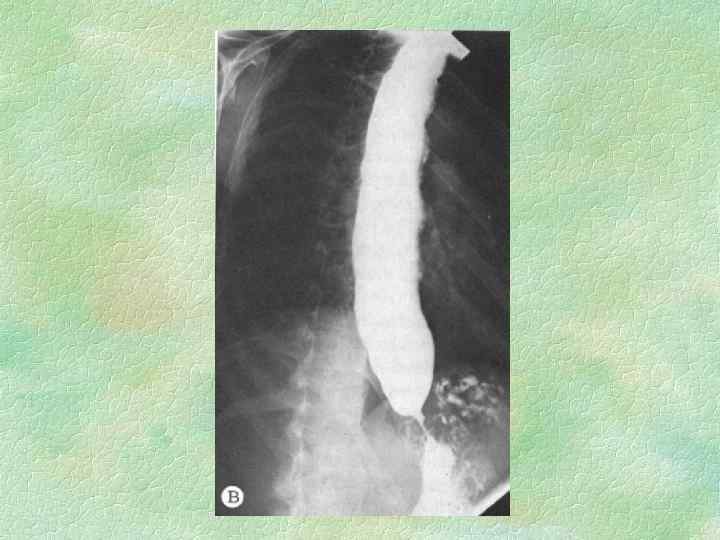

СТАДИИ КАРДИОСПАЗМА (Б. В. Петровский, 1962) I II IV непостоянный функциональный спазм без расширения пищевода постоянный спазм с незначительным расширением пищевода рубцовые изменения и органический стеноз с выраженным расширением пищевода резкий стеноз, удлинение и S-образная деформация пищевода